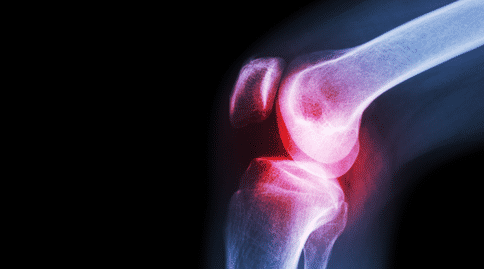

幼年特發(fā)性關(guān)節(jié)炎是兒童中常見的風濕病,但它表現(xiàn)為多種不同的形式,嚴重程度較高,且預(yù)后較差。這種疾病的多樣性不利于醫(yī)生對患者的治療,尤其是在疾病早期,醫(yī)生很難辨別疾病的類型,效果較差。

多關(guān)節(jié)炎型:女孩多見,起病年齡有2個高峰,1~3歲和青春早期。受累關(guān)節(jié)≥5個,尤以指趾小關(guān)節(jié)受累比較突出。起病緩慢或急驟,表現(xiàn)為關(guān)節(jié)僵硬、腫痛和局部發(fā)熱,一般很少發(fā)紅。

通常從大關(guān)節(jié)開始,如膝、踝、肘,逐漸累及小關(guān)節(jié),出現(xiàn)梭狀指。約1/2病兒頸椎關(guān)節(jié)受累,致頸部活動受限。顳頜關(guān)節(jié)受累造成咀嚼困難。少數(shù)發(fā)生環(huán)、杓(喉部軟骨)關(guān)節(jié)炎,致聲啞及喉喘鳴。晚期可出現(xiàn)髖關(guān)節(jié)受累及股骨頭破壞,發(fā)生運動障礙。關(guān)節(jié)癥狀反復(fù)發(fā)作、持續(xù)數(shù)年者關(guān)節(jié)僵直變形,關(guān)節(jié)附近肌肉萎縮。

少關(guān)節(jié)炎型:通常在1~3歲起病,受累關(guān)節(jié)不超過四個。膝關(guān)節(jié)經(jīng)常受累,其次是踝關(guān)節(jié),再次是手的小關(guān)節(jié),但幾乎任何關(guān)節(jié)均可受累。約20%的少關(guān)節(jié)型JIA患兒發(fā)生虹膜睫狀體炎,抗核抗體陽性患兒更易發(fā)生。